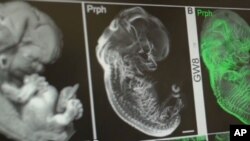

สำนักข่าวเอพีรายงานว่า ในช่วงต้นเดือนตุลาคมที่ผ่านมา สถาบันวิทยาศาสตร์แห่งชาติสหรัฐฯ (The National Academy of Sciences) ที่ได้รับเงินอุดหนุนกว่า 85% จากรัฐสภาอเมริกัน ลงวิดีโอและข้อความผ่านสื่อสังคมออนไลน์อย่างทวิตเตอร์ ที่มีเนื้อหาหมิ่นเหม่ต่อจริยธรรมด้านวิทยาศาสตร์ เกี่ยวกับการปรับแต่งพันธุกรรมในมนุษย์ และการสร้างเด็กทารกที่ “สมบูรณ์แบบ” ก่อนทีมงานจะตัดสินใจลบทวีตดังกล่าวทิ้ง

เนื้อหายังบอกด้วยว่าความคิดเรื่องการปรับแต่งพันธุกรรมอาจจะไม่ใช่นิยายวิทยาศาสตร์อีกต่อไป ในทวีตวิดีโอเจ้าปัญหานี้ยังมีคลิปที่ นักวิทยาศาสตร์เจนิเฟอร์ ดาวด์น่า (Jennifer Doudna) จากมหาวิทยาลัยแคลิฟอร์เนีย เบิร์คลีย์ ผู้บุกเบิกการปรับแต่งพันธุกรรมในมนุษย์กำลังถกประเด็นวิทยาศาสตร์รวมอยู่ด้วย

ในปีที่แล้ว พ.ศ. 2561 หน่วยงานวิจัยจากประเทศจีนประกาศว่าได้ปรับแต่งพันธุกรรมทารก แฝดคู่หนึ่ง ก่อนจะถูกวิพากษ์วิจารณ์อย่างมาก จนองค์การอนามัยโลก (World Health Organization) พร้อมทั้งสถาบันการศึกษาต่างๆ ต้องจัดตั้งคณะทำงานด้านวิทยาศาสตร์ขึ้นมา เพื่อศึกษา ดูแล และนำไปสู่การตรวจสอบควบคุมในอนาคต เนื่องจากการปรับแต่งพันธุกรรมในระดับดีเอ็นเอที่เกี่ยวพันธ์กับเสปิร์ม รังไข่ หรือ ตัวอ่อน จะส่งผลในระยะยาวถึงมนุษย์รุ่นต่อๆ ไป